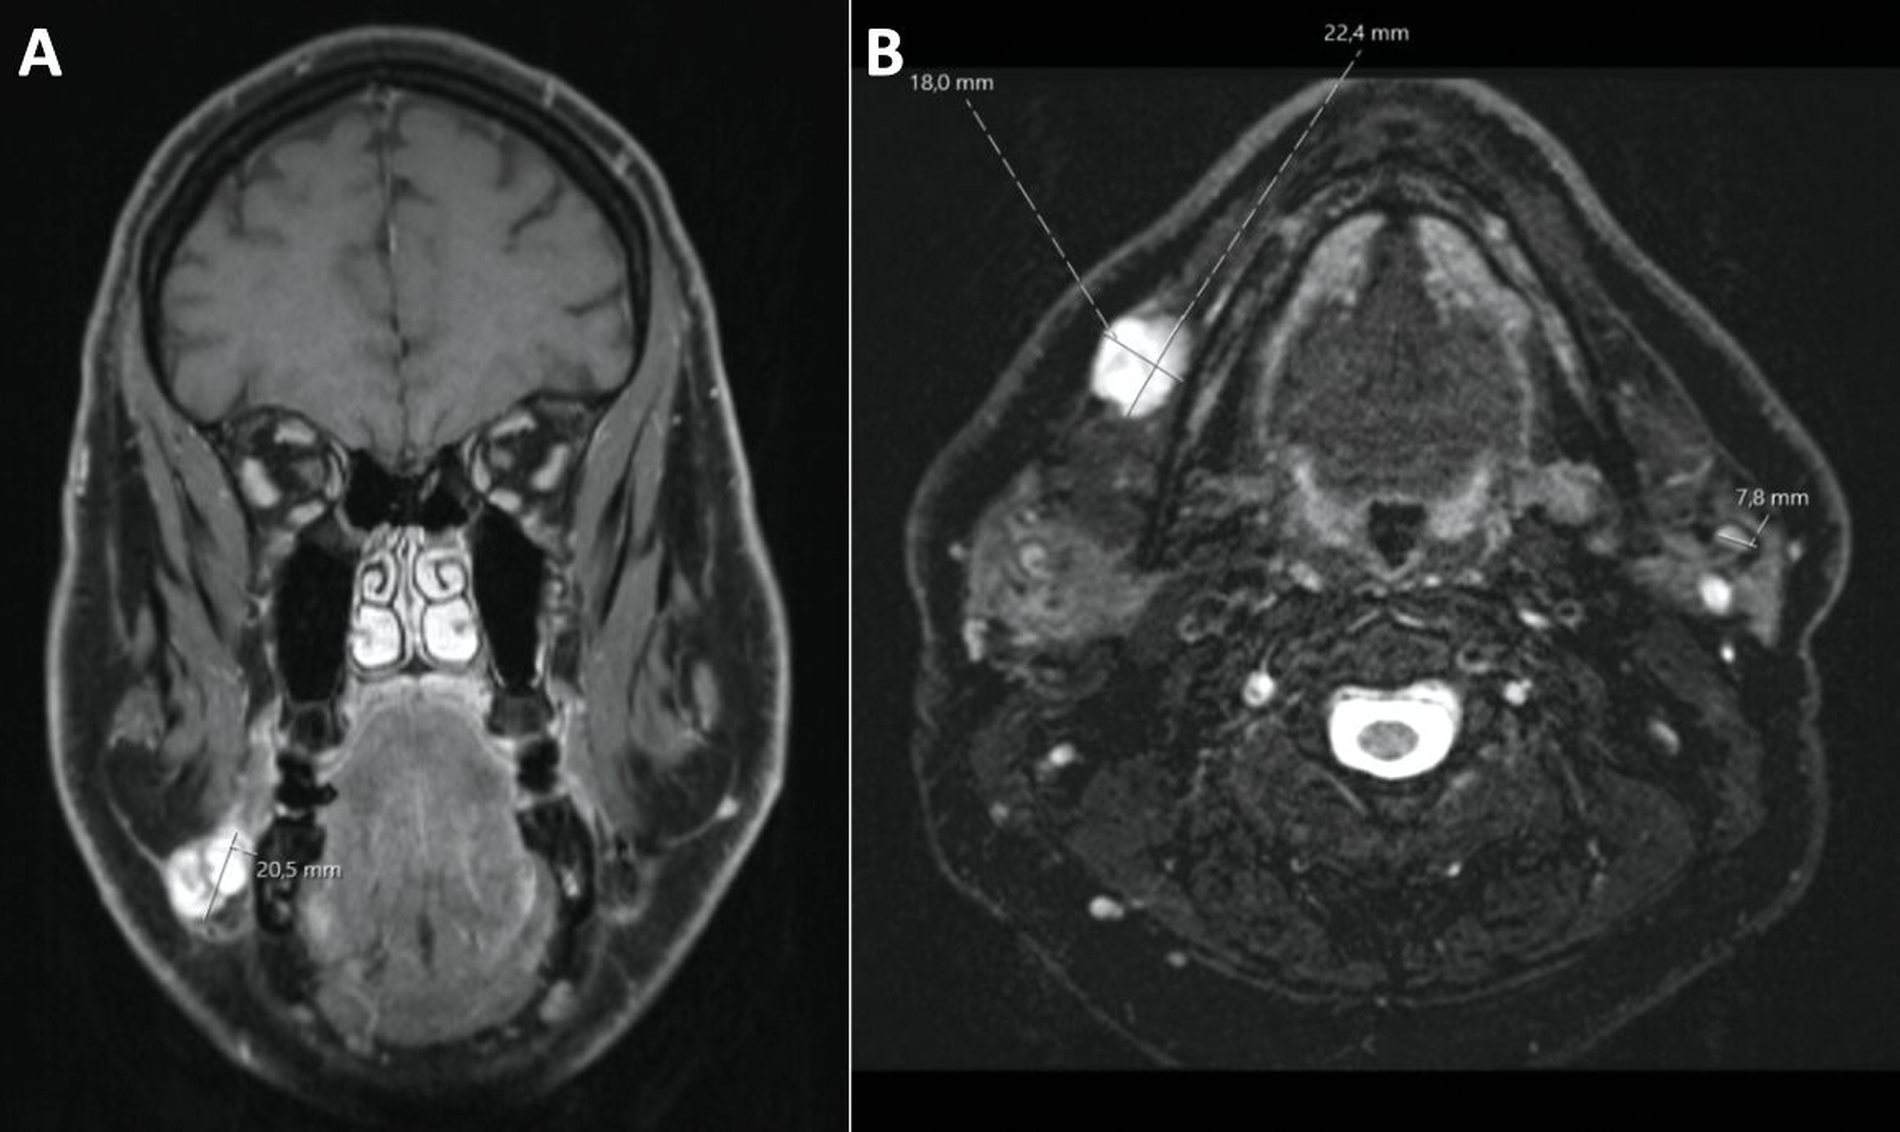

Sonografisch ließ sich eine 11,8 mm x 17,4 mm messende, scharf begrenzte, echoarme Raumforderung ohne nachweisliche Vaskularisierung mit dezenter dorsaler Schallverstärkung darstellen (Abbildung 1). Aufgrund des ungewöhnlich schnellen Wachstums erfolgte zum Ausschluss einer malignen Ursache sowie einer differenzialdiagnostisch in Betracht gezogenen Speichelretentionszyste die radiologische Bildgebung in Form eines Kontrastmittel-verstärkten MRTs. Dabei zeigte sich eine multilobulierte Läsion ventral am Musculus masseter ohne pathognomonische Morphologie, die in nativer T1-Wichtung isointens zum subkutanen Fettgewebe imponierte, mit flächiger Signalsteigerung nach Kontrastmittelgabe (Abbildung 2). Korrelierend dazu wurde eine deutliche restriktive Diffusionsstörung nachgewiesen, weshalb differenzialdiagnostisch nun vorrangig maligne Raumforderungen wie ein Liposarkom oder ein adenoidzystisches Karzinom diskutiert wurden. Eine (teil-)thrombosierte vaskuläre Malformation wurde allerdings ebenso in Betracht gezogen.